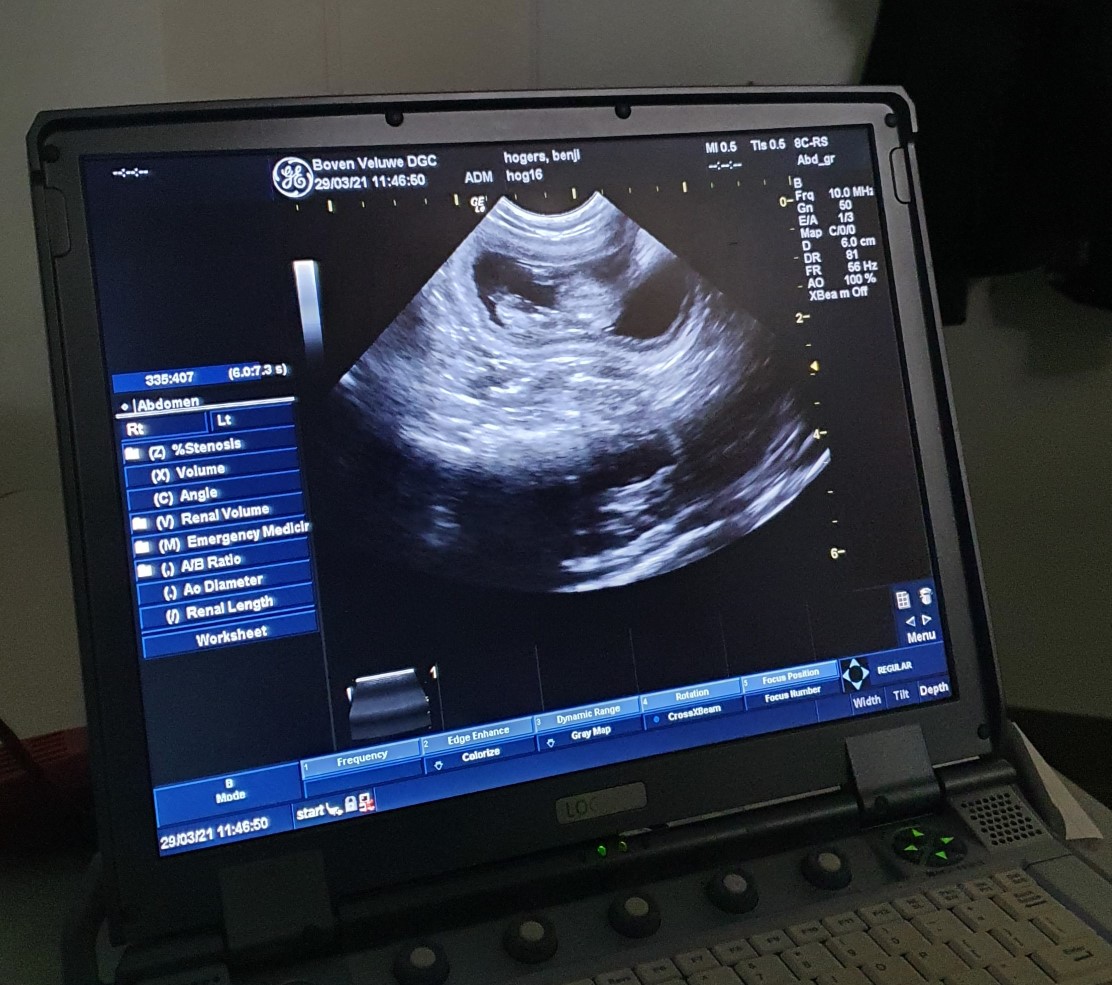

| het grote zwarte vlak binnen het grijs is

de vruchtblaas met het vruchtwater, het rode en blauw is de

bloedsstroom in het hartje van het kitten |

De echo is gemaakt met een apparaat uit het humane

ziekenhuis. De beelden zijn dan ook met een 2 verschillende koppen

gemaakt, waardoor er ook heel gedetailleerde beelden zijn.